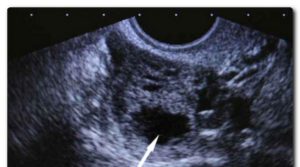

На раннем сроке, до 12 недель, УЗИ таза показывает только факт беременности — наличие плодного яйца внутри матки. Снимок показывает плодное яйцо как темное пятно округлой формы, имеющее светлый ободок и неоднородную структуру.

Яйцо может обнаруживаться и внутри маточной трубы. Так диагностируют внематочную беременность. Очень редко зародыш выходит в брюшную полость, где способен прикрепиться к внутренним органам.